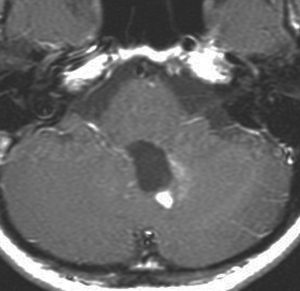

小脳毛様細胞性星細胞腫のFLAIR画像所見

壁在結節を伴うのう胞性小脳毛様細胞性星細胞腫は,結節を手術摘出すれば治癒するものです。しかし,あたかも腫瘍が残っているようなMRI画像所見が残ることがあります。

この例は,10歳の子どもに無症状で偶然発見された大きなのう胞性小脳毛様細胞性星細胞腫です。開頭手術で腫瘍結節は全摘出して腫瘍のう胞は縮小したままです。(画像はクリックすると拡大して見えます)

開頭手術で白く増強される結節部分だけを摘出しました。MIB-1はやや高値で3%と報告されました。病理組織診断は,WHO grade 1 毛様細胞性星細胞腫です。

6年後のMRI FLAIR画像です。摘出腔周囲の高信号域が残存しています。ここまで残ると腫瘍周辺浮腫ではありませんし,腫瘍細胞が左小脳半球に広範囲に浸潤して残存しているものだと判断されます。しかし,6年間で病変の増大傾向がありませんでした。この残存腫瘍(らしい所見)に対して放射線治療や化学療法を行うべきかどうか,結論は出ていません。しかし,経過観察を続けても増大して来ない例があることは確かです。一方で,この高信号領域が拡大したり,ガドリニウム増強される病変が再出現して治療がまた必用となることもあります。